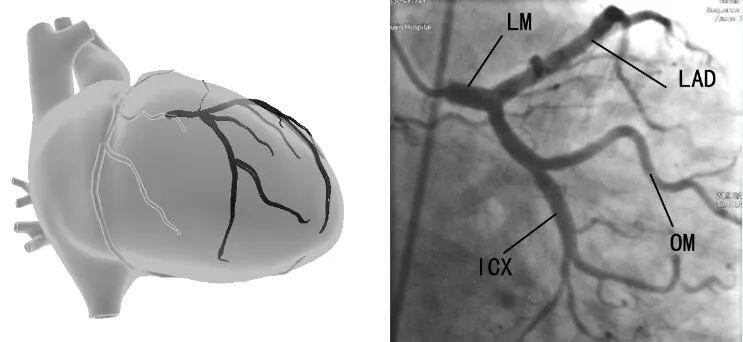

左旋支 (left circumflex lcx)

冠状动脉造影 观察lad,lcx起始部,lcx全程,钝缘支(om) 全程 右前斜